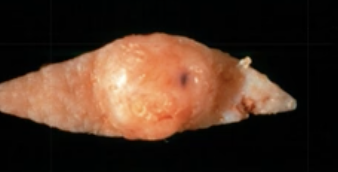

cyst

發育型

| Dentigerous cyst (DC) | follicle 分離 | 38,48 | 10 - 30y |

| Eruption cyst (EC) | Dentigerous 萌發 | 12a, 12b, 34a, ?6 | 10y ↓ | 藍色或紫棕色   |

| Odontogenic Keratocyst cyst (OKC) |

下顎骨後端,下齒槽管上方 | 10-40y | 組生齒(40%) | |

| Radiolucent、 MD方向下顎骨吸收,但牙根完整。  |